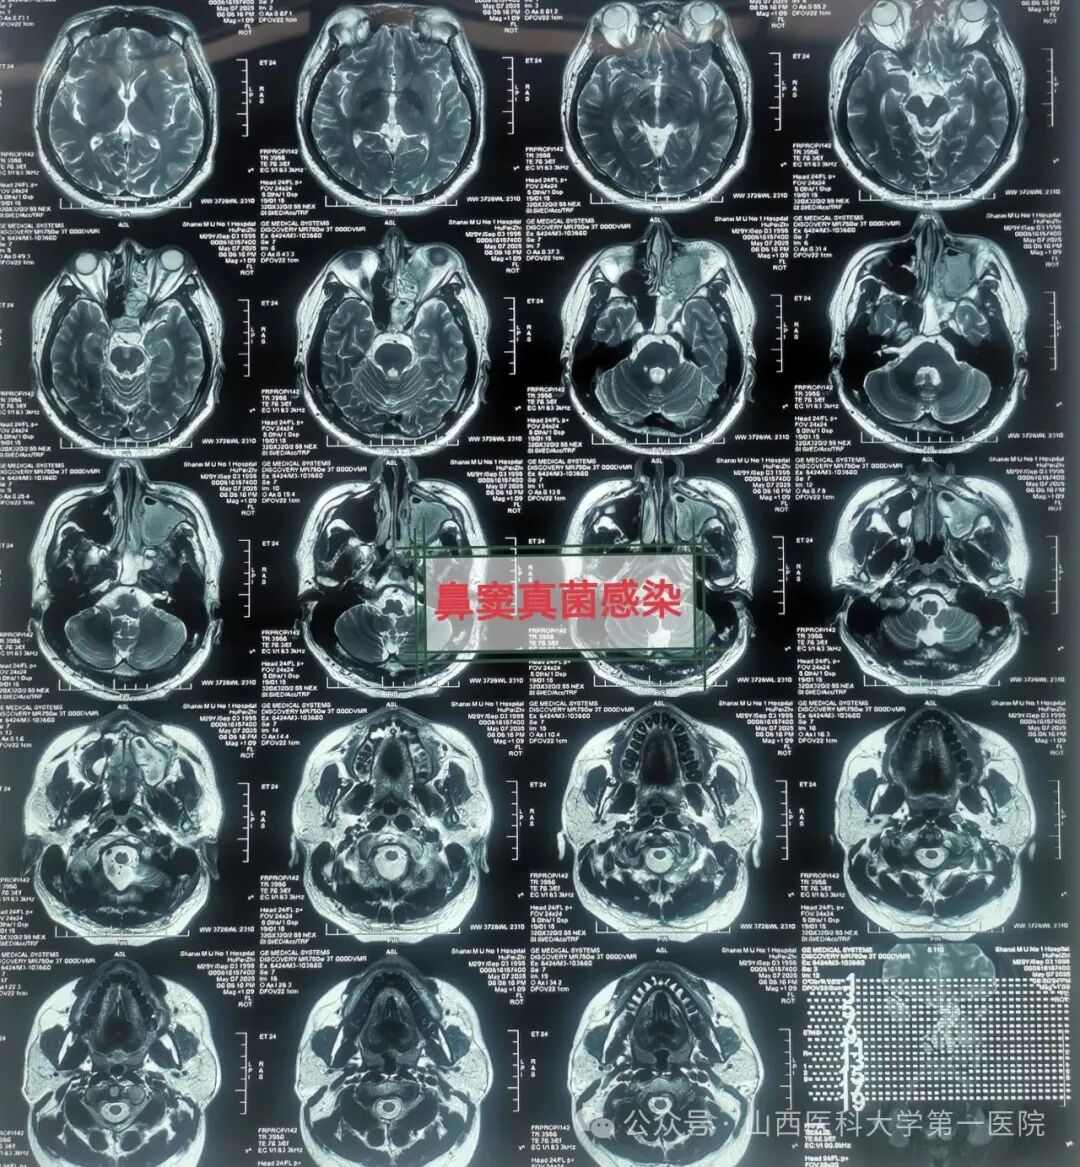

49岁的袁先生过敏性鼻炎多年,合并糖尿病与痛风,一直药物维持治疗;2年前因合并鼻窦炎,口服药物治疗效果不佳;近数月以来病情逐渐加重,鼻塞流涕,最近头痛头闷症状越来越严重同时出现鼻涕带血丝,就诊于山西医科大学第一医院耳鼻咽喉-头颈外科,确诊为鼻窦真菌感染,医生通过手术切除鼻腔病变组织,清除霉菌团块,开放鼻窦,引流分泌物,清洗术腔,重建鼻腔结构、恢复功能,改善并缓解了临床症状。

耳鼻咽喉-头颈外科皇甫辉教授介绍,真菌性鼻窦炎是临床常见的特异性感染性疾病,近年来发病率有上升趋势,可能与抗生素广泛使用、环境污染等有关,而糖尿病、抗肿瘤药物治疗、放疗以及长期使用激素等是真菌性鼻窦炎的高发人群。真菌性鼻窦炎通常分非侵袭型真菌性鼻-鼻窦炎与侵袭型真菌性鼻-鼻窦炎两类,非侵袭型真菌性鼻-鼻窦炎之病变局限在鼻窦腔内,粘膜和骨壁内却无真菌侵犯;而侵袭型真菌性鼻-真窦炎是真菌感染不仅位于鼻腔,同时侵犯鼻窦粘膜和骨壁,并向鼻窦外周围结构和组织如眼眶、前颅底或翼腭窝等侵袭发展,一般情况下,侵袭型真菌性鼻-真窦炎预后凶险。

皇甫辉讲到,低免疫功能、低氧及高血糖环境是真菌生存合适条件,局部因素也是部分真菌性鼻窦炎主要致病因素之一,各因素所致鼻腔鼻窦通气引流受阻,解剖因素如中鼻道狭窄、中鼻甲反向偏曲等,局部炎症水肿,窦腔分泌物潴留,同侧上列牙齿病变等。真菌性鼻-鼻窦炎侵袭型者一经确诊,应尽早手术,清除鼻腔和鼻窦内真菌病原和坏死及不可逆之病变组织,恢复鼻腔鼻窦通畅引流,病变范围广者可采用柯-陆氏手术、与鼻内镜手术联合等术式,病变累及颅内时可采用颅面联合术式,术前应用抗真菌药物治疗,术后可应用抗真菌药物冲洗鼻腔和鼻窦等。